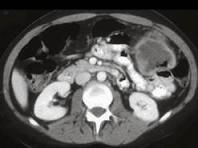

男,55岁,腹部胀痛不适一月余,CT检查如图,最可能的诊断是 ( )A.结肠结核B.结肠淋巴瘤C.结肠转移瘤D.假膜性结肠炎E.横结肠癌

问题 男,55岁,腹部胀痛不适一月余,CT检查如图,最可能的诊断是 ( )

选项 A.结肠结核 B.结肠淋巴瘤 C.结肠转移瘤 D.假膜性结肠炎 E.横结肠癌

答案 E